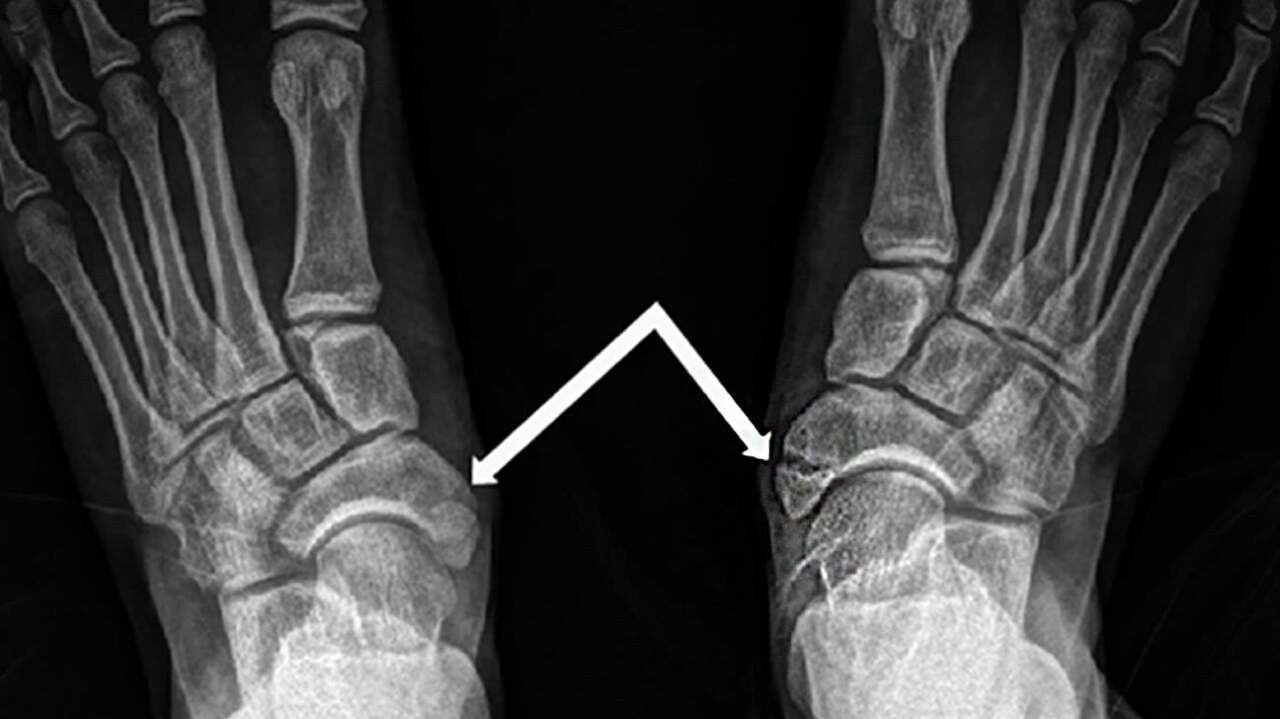

기타 골절 수술

5th metatarsal bone fracture